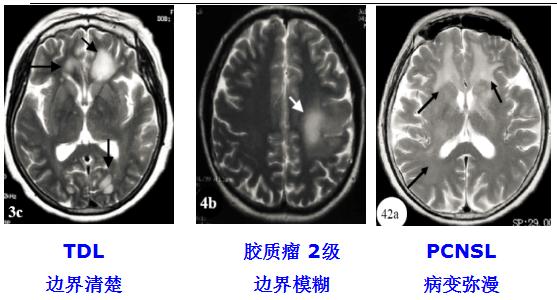

5. TDL与胶质瘤、PCNSL的影像对比

图 MRI平扫

(1)TDLs的MRI-T2WI往往边界清楚,胶质瘤的MRI-T2WI边界相对模糊。

(3)TDL较特异:同心圆样病灶、增强MRI的动态演变、开环样强化、垂直于侧脑室的“梳齿征”及云片状T2病灶,边界较清楚,伴短T2边缘。